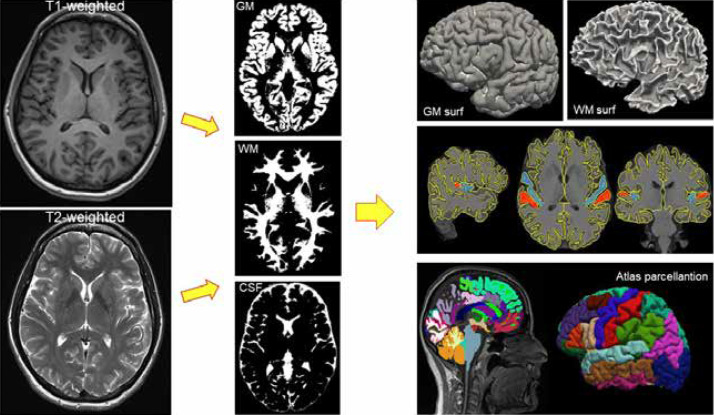

定量磁共振成像(MRI)容量法已成为现代神经病学的关键组成部分,弥合了详细神经成像和临床决策之间的差距。通过采用先进的成像技术,如3D t1加权、t2加权和液体衰减反转恢复(FLAIR)序列,MRI容量测定使临床医生能够客观地量化与阿尔茨海默病、多发性硬化症、癫痫和肌强直性营养不良等神经系统疾病相关的脑容量变化。自动分割工具,包括FreeSurfer、NeuroQuant、volBrain和AccuBrain,促进了对大脑结构变化的精确和可重复的分析,对早期诊断、患者监测和治疗计划做出了重大贡献。在阿尔茨海默病中,体积MRI可以检测早期海马和颞叶萎缩,为诊断和监测疾病进展提供重要的生物标志物。同样,在多发性硬化症中,体积分析量化了灰质和白质退化,反映了运动和认知障碍的严重程度。此外,定量MRI技术精确地描绘了癫痫的结构异常,如海马硬化和局灶性皮质发育不良,这对准确的手术干预至关重要。人工智能和机器学习的持续进步将进一步增强这些体积方法,解决当前的局限性,如观察者之间的可变性,并扩大其临床适用性。这篇综述概述了定量MRI体积测量的现状和未来发展轨迹,强调了其在临床神经病学和个性化医学中的扩展作用。

Quantitative magnetic resonance imaging (MRI) volumetry has become a pivotal component in modern neurology, bridging the gap between detailed neuroimaging and clinical decision-making. By employing advanced imaging techniques like 3D T1-weighted, T2-weighted, and fluid-attenuated inversion recovery (FLAIR) sequences, MRI volumetry enables clinicians to objectively quantify brain volume changes associated with neurological conditions such as Alzheimer's disease, multiple sclerosis, epilepsy, and myotonic dystrophy. Automated segmentation tools, including FreeSurfer, NeuroQuant, volBrain, and AccuBrain, facilitate precise and reproducible analysis of structural brain changes, contributing significantly to early diagnosis, patient monitoring, and therapeutic planning. In Alzheimer's disease, volumetric MRI enables the detection of early hippocampal and temporal lobe atrophy, providing a crucial biomarker for diagnosis and monitoring disease progression. Similarly, in multiple sclerosis, volumetric analyses quantify grey and white matter degeneration, reflecting motor and cognitive impairment severity. Moreover, quantitative MRI techniques precisely delineate structural abnormalities like hippocampal sclerosis and focal cortical dysplasia in epilepsy, crucial for accurate surgical intervention. Ongoing advances in artificial intelligence and machine learning are set to further enhance these volumetric approaches, addressing current limitations such as inter-observer variability and expanding their clinical applicability. This review outlines the existing landscape and future trajectory of quantitative MRI volumetry, underscoring its expanding role in clinical neurology and personalised medicine.